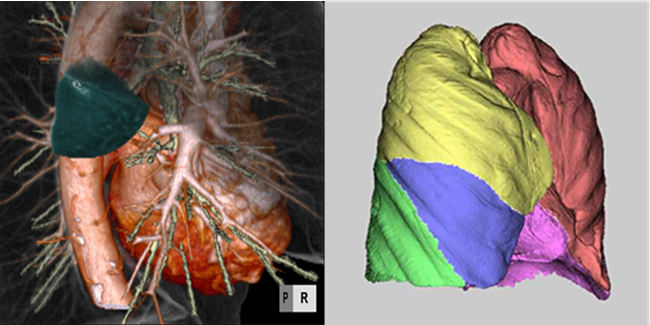

【胸部CT画像のコンピュータ支援診断(CAD)の開発と人工知能の応用】

従来、胸部CT診断は放射線科医による視覚的・質的診断が主流であったが、マルチスライスCTの登場以降、大量の画像データを人間の力だけで処理するのが困難になりつつある。当教室では胸部CT画像をコンピュータ解析することによって疾患を定量値として表示し、読影を補助するCADを呼吸器内科、呼吸器外科、工学部、企業と共同で数多く開発してきた。これまでに開発した主なCADは1) 肺癌の形態、内部性状、3D容積計測、2) バーチャルブロンコスコピーによる気管支鏡診断支援、3) 3D-CT Angiographyを使ったバーチャル肺癌区域切除術、4) 肺葉自動分割CADなどがある。最近では人工知能(deep learning)による胸部CT診断の研究にも取り組んでいる。